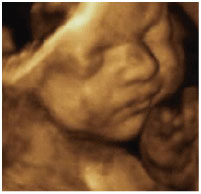

4Dエコーとは、3Dエコーに時間の要素を加えたものです。従来の2Dエコーでは断面的にしか見えなかった赤ちゃんの画像が、4Dエコーを導入してからはリアルタイムで動画として抽出できるようになりました。

週数によってお腹の中の赤ちゃんの顔や手足の様子がはっきりとわかります。

4Dエコーで見た胎児の様子。

当院設置の4D映像です。